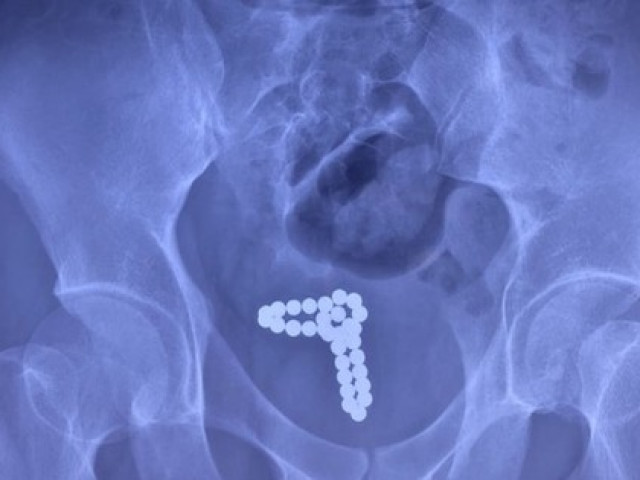

Qua thăm khám, dựa trên các xét nghiệm siêu âm và phim chụp X-quang, các bác sĩ phát hiện ra một đoạn keo nến cuộn trong bàng quang và một phần tại niệu đạo. Các bác sĩ Khoa Nam học đã nhanh chóng tiến hành nội soi bàng quang để lấy dị vật ra ngoài cho bệnh nhân.

Kết quả, đã lấy được một cây keo nến đã bị gãy thành 3 đoạn, với tổng chiều dài 40cm. Bên cạnh đó, trong khi thực hiện lấy bỏ dị vật ra ngoài, bác sĩ nhận thấy niêm mạc bàng quang, và niệu đạo đã có hiện tượng viêm đỏ. Một vài điểm có tổn thương niêm mạc niệu đạo.